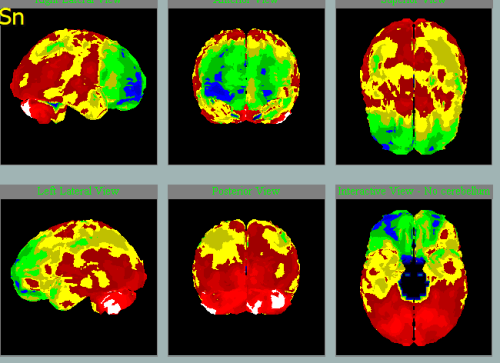

V letech je možné vidět přibývání hypoperfúze a tedy progresi:

2011

2014

2020